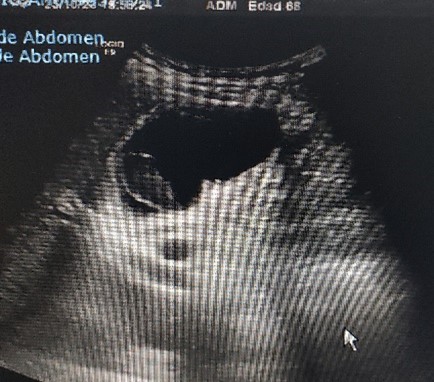

ECOGRAFIA CLÍNICA:  Se aprecia vesicular biliar bien repleccionada con imagen en su interior redondeada, hipoecoica, sin sombra, Murphy ecográfico positivo.

La clínica ya orienta el diagnostico pero la Ecografia filia el origen.

Lo llamativo para mi del caso fue visualizar un calculo biliar sin sombra (calculo blando) , saber de su caracteristicas ecograficas y tenerlo como opción diagnóstica.